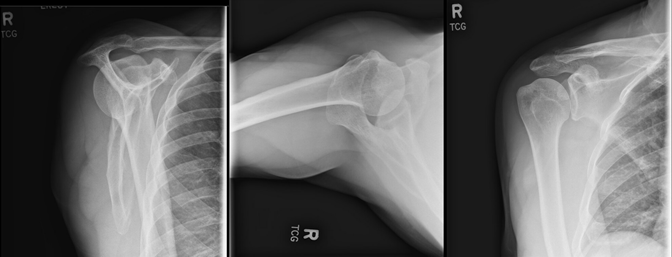

A 68-year-old male presented with complaints of the right shoulder pain over the previous 6 months after a fall from his bicycle. Following negative X-rays (Fig. 1), he initially elected to proceed with an intra-articular injection and physical therapy, with plans to obtain a magnetic resonance imaging (MRI) if no improvement occurred. He noted initial improvement but returned 6 months later due to recurrence of pain. Subsequent MRI revealed a full-thickness tear of the supraspinatus tendon with 4.5 cm of retraction, as well as tendinosis of the infraspinatus, subscapularis, and biceps tendon.

Figure 1: X-ray lateral, superior-inferior axial, and anteroposterior view. Joint bases are well preserved without significant osteoarthritis. No fractures, dislocation, or loose body seen.